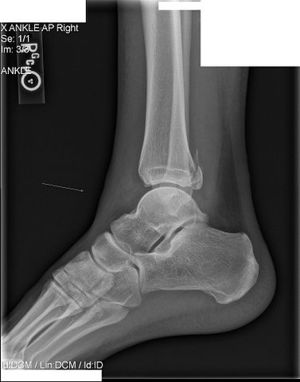

Maisonneuve fracture

Evaluation

- Increase in medial clear space of ankle joint

- Tibiofibular clear space widened >5mm

- High fibular fracture

- Signs of syndesmotic injury